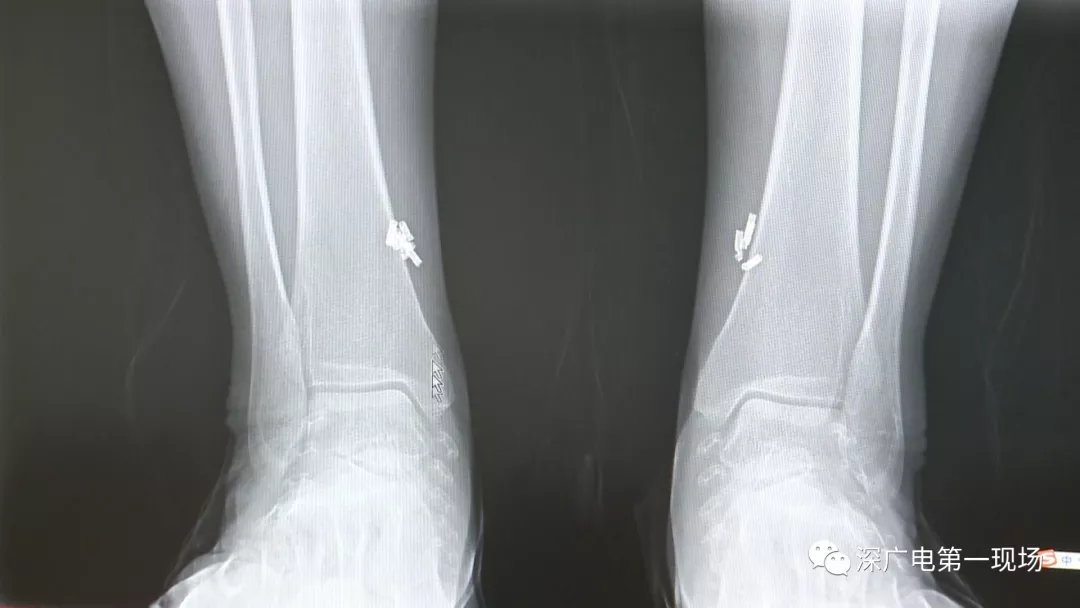

深圳一女子全身被植入彈簧圈,數(shù)量多到驚人!竟是為治這病…

出于保護患者,我們沒有直接采訪,但是通過醫(yī)生的介紹,記者了解到,病人是個36歲的女性,2歲開始就有癲癇病史,而且藥物治療也并不見效。

多方打聽之后,在山東某診所用全身埋彈簧圈的方式治療癲癇。陶主任介紹,這樣的方式想要治愈,那幾率也等同于撞大運??!